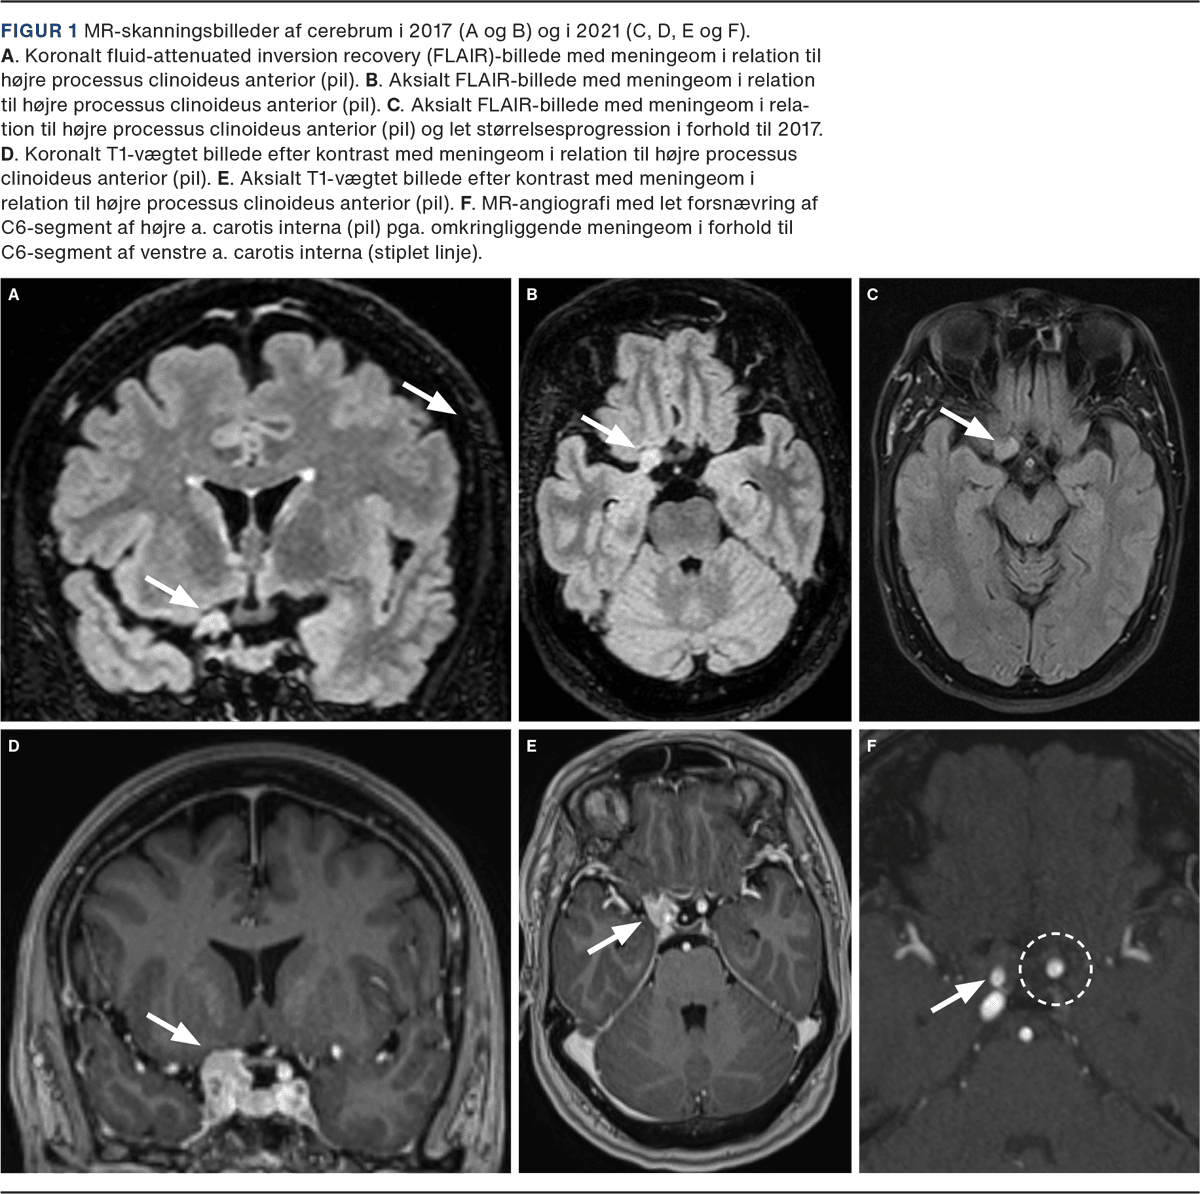

Patienten var en 54-årig kvinde, som tidligere var blevet diagnosticeret med hypertension og dyslipidæmi, havde haft to episoder af formodet vaskulær genese med ensidige sensomotoriske strokelignende symptomer og kraftig hovedpine. Man havde dengang fundet det i uoverensstemmelse med normale forhold på en MR-skanning af cerebrum Figur 1 A og B.

Dog blev der set en ekstraaksial forandring lokaliseret i relation til sella turcica på højre side. Der blev derfor undersøgt med MR-skanning af cerebrum med angiografi (Figur 1 C-F), hvor der sås en lille proces i relation til højre PCA, hvilket var foreneligt med meningeom, og ud fra beskrivelsen kunne det ses, at meningeomet også var synligt på de tidligere MR-skanninger, men var blevet overset. Der fandtes normale blodprøver og ingen halskaranomalier, kardial embolikilde, arytmi eller hyperkoagulable tilstande. Knap tre mdr. senere blev der foretaget kirurgisk fjernelse af et højresidigt meningeom ved PCA. Den seneste opfølgning var 16 mdr. efter indgrebet, og her var patienten symptomfri.